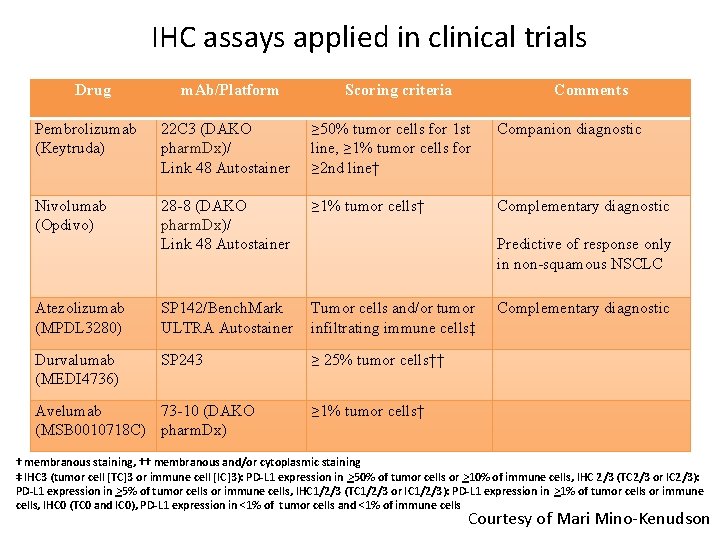

IHC assays applied in clinical trials Drug m. Ab/Platform Scoring criteria Comments Pembrolizumab (Keytruda) 22 C 3 (DAKO pharm. Dx)/ Link 48 Autostainer ≥ 50% tumor cells for 1 st line, ≥ 1% tumor cells for ≥ 2 nd line† Companion diagnostic Nivolumab (Opdivo) 28 -8 (DAKO pharm. Dx)/ Link 48 Autostainer ≥ 1% tumor cells† Complementary diagnostic Predictive of response only in non-squamous NSCLC Atezolizumab (MPDL 3280) SP 142/Bench. Mark ULTRA Autostainer Tumor cells and/or tumor infiltrating immune cells‡ Complementary diagnostic Durvalumab (MEDI 4736) SP 243 ≥ 25% tumor cells†† ≥ 1% tumor cells† Avelumab 73 -10 (DAKO (MSB 0010718 C) pharm. Dx) † membranous staining, †† membranous and/or cytoplasmic staining ‡ IHC 3 (tumor cell [TC]3 or immune cell [IC]3): PD-L 1 expression in >50% of tumor cells or >10% of immune cells, IHC 2/3 (TC 2/3 or IC 2/3): PD-L 1 expression in >5% of tumor cells or immune cells, IHC 1/2/3 (TC 1/2/3 or IC 1/2/3): PD-L 1 expression in >1% of tumor cells or immune cells, IHC 0 (TC 0 and IC 0), PD-L 1 expression in <1% of tumor cells and <1% of immune cells Courtesy of Mari Mino-Kenudson

FDA-approved Companion Diagnostics in NSCLC Diagnosis Mutation/Target Drug Diagnotic NSCLC EGFR Erlotinib Gefitinib Afatinib Roche Cobas Qiagen Therascreen NSCLC EGFR T 790 M Osimertinib Roche Cobas V 2 NSCLC ALK Crizotinib Alectinib Ceritinib Abbott FISH; Ventana IHC D 5 F 3 FDA-Approved* NSCLC ROS 1 Crizotinib MGH FISH* NSCLC PD 1 Pembrolizumab PDL 1 IHC (DAKO) Source: FDA website